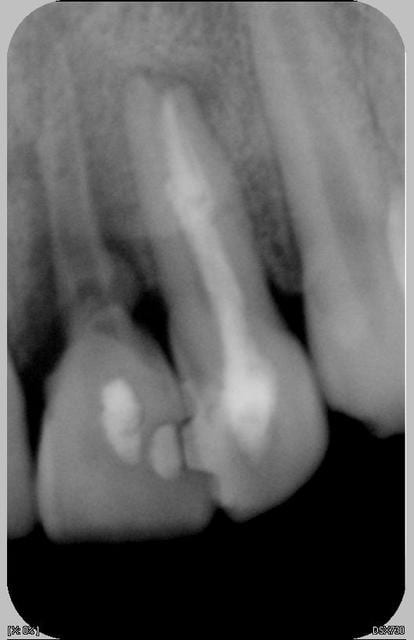

Suite du traitement

ouverture de la 11

nettoyage + EDTA-Hypochlorite sous ultrason

appareil provisoire sous le coude

la 11 n'est plus mobile

la patiente part pour deux mois, revient en septembre